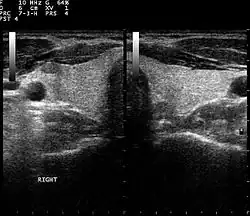

Muscoesqueleto

Tendones, músculos, nervios, ligamentos, masas de tejidos blandos y superficies óseas. Es una alternativa a la radiografía en la detección de fracturas de muñeca, codo y hombro para pacientes de hasta 12 años.

Endocrinología, laringología

La mayoría de las estructuras del cuello, incluyendo las glándulas tiroides y paratiroides, los ganglios linfáticos y las glándulas salivales, se visualizan bien mediante ultrasonidos de alta frecuencia con imágenes de alta calidad. La ecografía es una modalidad de imagen con especial incidencia en lesiones de tiroideas.[19]

Muchas otras condiciones benignas y malignas en la cabeza y el cuello pueden ser evaluadas y manejadas con la ayuda de ultrasonido de diagnóstico y procedimientos guiados por ultrasonido.